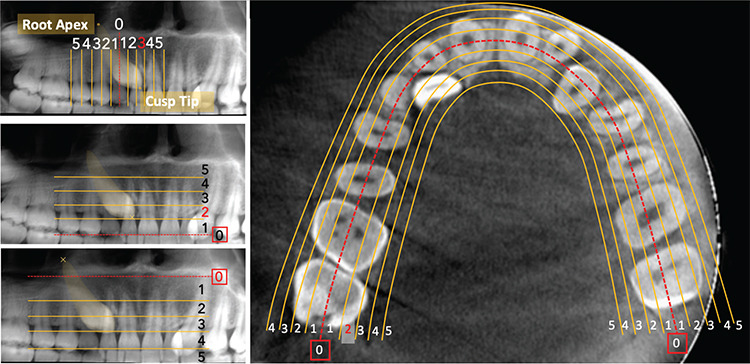

A thorough clinical and radiographical assessment of an impacted maxillary canine's location forms the basis for proper diagnosis and successful treatment outcomes. Implementing a correct biomechanical approach for directing force application primarily relies on its precise localization. Poor biomechanical planning can resorb the roots of adjacent teeth and result in poor periodontal outcomes of the canine that has been disimpacted. Furthermore, treatment success and time strongly rely on an accurate assessment of the severity of impaction, which depends on its 3D spatial location. The evolution of cone-beam computed tomography (CBCT) radiographs provides more detailed information regarding the location of the impacted canines. In addition, the literature has shown that CBCT imaging has enhanced the quality of diagnosis and treatment planning by obtaining a more precise localization of impacted canines. This review article highlights current evidence regarding comprehensive evaluation of three-dimensional orientations of impacted canines on CBCT images for precise diagnosis and treatment planning.